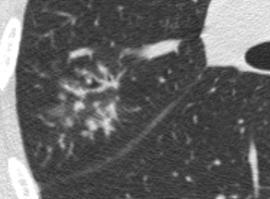

Airway disease - Centrilobular nodules

Rounded or irregular opacity, well or poorly defined, measuring up to 3 cm in diameter. Centrilobular nodules appear separated by several millimeters from the pleural surfaces, fissures, and interlobular septa. They usually are ill-defined, with soft-tissue or ground-glass attenuation, and size ranging from a few millimeters to one centimeter.